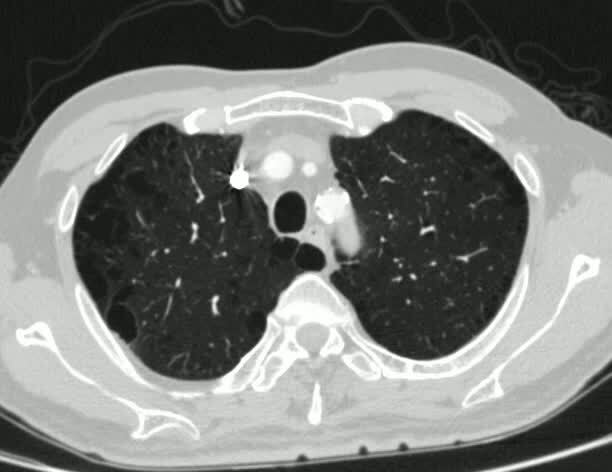

隨著對肺部結(jié)節(jié)認識的深入,我們知道磨玻璃結(jié)節(jié)在觀察中只要不消失,大多都是腫瘤性病變,但都具有惰性,發(fā)展緩慢,有些病人可能持續(xù)觀察多年沒有任何變化,當(dāng)然,也有些病人在觀察過程中出現(xiàn)了結(jié)節(jié)的增大或變實的情況。那么,問題來了,如果在觀察過程中出現(xiàn)了磨玻璃結(jié)節(jié)的增大或變實再進行手術(shù),相比一開始發(fā)現(xiàn)就進行手術(shù),是不是會影響手術(shù)效果?帶著這個問題,我試著檢索了一下資料,沒有發(fā)現(xiàn)有相關(guān)的研究報道。其實,這樣的研究是很難進行的,這個不難理解。從理論上說,如果已經(jīng)判定結(jié)節(jié)是個腫瘤,等它長大了再手術(shù)切除似乎并不合理,但鑒于目前所見的磨玻璃結(jié)節(jié)都有一定惰性的現(xiàn)實,在特定情況下似乎也是可行的。之前我在公眾號里曾講過一位病人發(fā)現(xiàn)肺部混合磨玻璃結(jié)節(jié)后,因為年齡原因未進行干預(yù),僅做定期隨訪,最后出現(xiàn)轉(zhuǎn)移的例子(一枚混合磨玻璃結(jié)節(jié)自然演變過程帶給我們的啟示)。這期給大家介紹幾個病例,分別是混合磨玻璃結(jié)節(jié)和純磨玻璃結(jié)節(jié)觀察增大的情況。先來看第一個病例:這是十多年前的病人,老年男性,79歲,胸部CT發(fā)現(xiàn)左肺上葉混合磨玻璃結(jié)節(jié),以實性成分為主,最大徑17mm,來胸外科就診。見下圖:????這枚結(jié)節(jié)看上去應(yīng)該是肺癌,我們查了一下,他在1年半以前也有CT,當(dāng)時也能看到這個結(jié)節(jié),但那時只有14mm,以磨玻璃為主,實性成份很少,當(dāng)時就應(yīng)該考慮為早期肺癌了,不知道為什么當(dāng)時沒有來胸外科就診。見下圖:????根據(jù)病人結(jié)節(jié)的形態(tài)特點和變化規(guī)律,應(yīng)該是肺癌沒有問題,但考慮到病人高齡,并且合并高血壓、糖尿病多年,所以當(dāng)時僅做了局部切除,術(shù)后病理報告為高分化腺癌(那時的病理報告還沿用高中低分化的說法)。術(shù)后病人也未做任何輔助治療,僅定期復(fù)查隨訪。5年半后病人因頸背部疼痛來院檢查治療,CT發(fā)現(xiàn)局部復(fù)發(fā),伴有多發(fā)頸椎、胸椎轉(zhuǎn)移,見下面的CT圖片:??下面是該CT上看到的多發(fā)椎體轉(zhuǎn)移破壞(頸椎破壞的片子與此類似,不再展示):??病人開始一系列對癥止痛治療,4個月后病人去世。這位病人如果在剛開始發(fā)現(xiàn)時就進行手術(shù)切除有沒有可能生存時間更長一些?畢竟經(jīng)過一年半的時間,結(jié)節(jié)明顯增大,從磨玻璃為主,變?yōu)閷嵭猿煞轂橹?,增長速度還是很快的,如果早切除或許會有更好的結(jié)果。當(dāng)時手術(shù)是局部切除,如果病人身體好些,進行更為徹底的肺葉切除或哪怕是肺段切除,會不會更好一點?或許可能,但世間萬物沒有如果!這個病例告訴我們,對于混合磨玻璃結(jié)節(jié),觀察時間不宜過長,觀察的目的是確認結(jié)節(jié)是否吸收、消失即可,不要等結(jié)節(jié)增大變實再進行手術(shù),否則可能會錯過最佳治療時機!上面的病人是混合磨玻璃結(jié)節(jié),對于純磨玻璃結(jié)節(jié)會是什么情況呢?我們再來看另外兩位病人:第一位是69歲老年男性,發(fā)現(xiàn)左肺上葉磨玻璃結(jié)節(jié)來診,最大徑11mm,內(nèi)有空泡,最高密度區(qū)域接近-450Hu,見下圖:?患者當(dāng)時是2020-5來住院治療的?;颊哂捎趦?nèi)科疾病曾多次住院,有多次胸部CT,我們仔細對比了病人結(jié)節(jié)部位的影像學(xué)表現(xiàn),可以發(fā)現(xiàn)2015-1胸部CT在左肺上葉局部尚難以發(fā)現(xiàn)異常,隨時間流逝,2017年局部開始出現(xiàn)陰影,2018年形成局部磨玻璃結(jié)節(jié)灶,之后結(jié)節(jié)逐漸增大、變濃,見下圖:?根據(jù)病人現(xiàn)有的影像資料,病人在5年前局部沒有結(jié)節(jié),從3年前開始出現(xiàn),短短幾年內(nèi),結(jié)節(jié)從無到有,逐漸長大,呈現(xiàn)持續(xù)增大、變實的趨勢。毫無疑問,不能任由結(jié)節(jié)持續(xù)發(fā)展下去,以免造成不可挽回的后果,最終病人進行了手術(shù)切除,術(shù)后病理為微浸潤腺癌。再來看另一位病人,54歲女性,2022-8胸部CT發(fā)現(xiàn)左肺上葉舌段磨玻璃結(jié)節(jié),最大徑20mm,密度不均勻,最高密度區(qū)域-280Hu左右,有血管穿行,見下圖:???病人2019年也做過胸部CT,也可以看到這枚結(jié)節(jié),但那時的結(jié)節(jié)明顯小很多。見下圖:?從2019年到現(xiàn)在,三年的時間,結(jié)節(jié)明顯增大。那就沒什么好說的了,應(yīng)盡早進行手術(shù)治療。由于結(jié)節(jié)位置靠內(nèi),我們?yōu)椴∪诉M行了肺段切除,術(shù)后也是微浸潤腺癌。這里簡單科普一下什么是微浸潤腺癌:從不典型腺瘤樣增生(癌前病變)開始,剛好發(fā)生癌變,沒有任何浸潤成份的是原位癌,不會有轉(zhuǎn)移;出現(xiàn)少量浸潤,浸潤范圍不超過5mm,稱為微浸潤腺癌,罕見淋巴結(jié)或遠處轉(zhuǎn)移。這兩位病人都是很幸運的,整個觀察過程中,盡管結(jié)節(jié)出現(xiàn)明顯增大,但最后病理都是微浸潤腺癌,按照我們目前對于肺癌的認知,這樣的腫瘤極少出現(xiàn)轉(zhuǎn)移,局部切除/或肺段切除就足以達到類似于治愈的效果。所以,對于這兩位病人來說,結(jié)節(jié)增大對于他們的預(yù)后可能影響不會太大。但有一點需要強調(diào),那就是隨訪中初次察覺到結(jié)節(jié)增大就建議處理掉,而不是等到結(jié)節(jié)增大到某一臨界值才下決心,因為我們很難預(yù)測下一步結(jié)節(jié)的增長速會是怎樣,只要結(jié)節(jié)有增大或變濃的趨勢,就說明結(jié)節(jié)不穩(wěn)定,盡管從形態(tài)、密度上判斷可能處于微浸潤癌、甚至在原位癌階段,也不建議繼續(xù)觀察下去,因為這些結(jié)節(jié)很可能會越長越快,最終可能釀成難以挽回的后果。對于隨訪觀察中穩(wěn)定的純磨玻璃結(jié)節(jié),只要密度很低,大多數(shù)人出于對手術(shù)的天然的恐懼,可以考慮持續(xù)動態(tài)觀察到出現(xiàn)變化再進行處理,而對于密度偏高的磨玻璃結(jié)節(jié),不建議無休止的觀察下去,無論其直徑大小,因為這些結(jié)節(jié)即便直徑很小,不但可能是浸潤癌,還有極小的概率出現(xiàn)轉(zhuǎn)移(參見公眾號文章:磨玻璃結(jié)節(jié)到底會不會出現(xiàn)淋巴結(jié)轉(zhuǎn)移?;磨玻璃結(jié)節(jié)到底有沒有可能轉(zhuǎn)移?)。綜合上面三位病人的診治過程,對于混合磨玻璃結(jié)節(jié),只要排除了非腫瘤性疾病,建議盡早處理,不建議長時間觀察;對于純玻璃結(jié)節(jié)來說,對于部分病人來說,如果密度很低(最高值最好也在-600Hu以下),可以考慮觀察到結(jié)節(jié)有增大或變濃的趨勢再進行處理,或許對治療效果影響不大,但一定要在發(fā)覺變化后盡快處理;而對于密度偏高的磨玻璃結(jié)節(jié),只要感覺可能到了浸潤性癌的階段,盡管觀察期間穩(wěn)定無變化,也不建議無休止的觀察下去,而是盡可能處理掉,以免養(yǎng)虎為患。細心的朋友可能會發(fā)現(xiàn),第三位病人的片子上可以看到右肺也有磨玻璃結(jié)節(jié)。沒錯,這位病人是雙肺多發(fā)結(jié)節(jié),有好多病人都是這種情況的。多發(fā)結(jié)節(jié)該如何應(yīng)對?以后有機會再為大家科普。